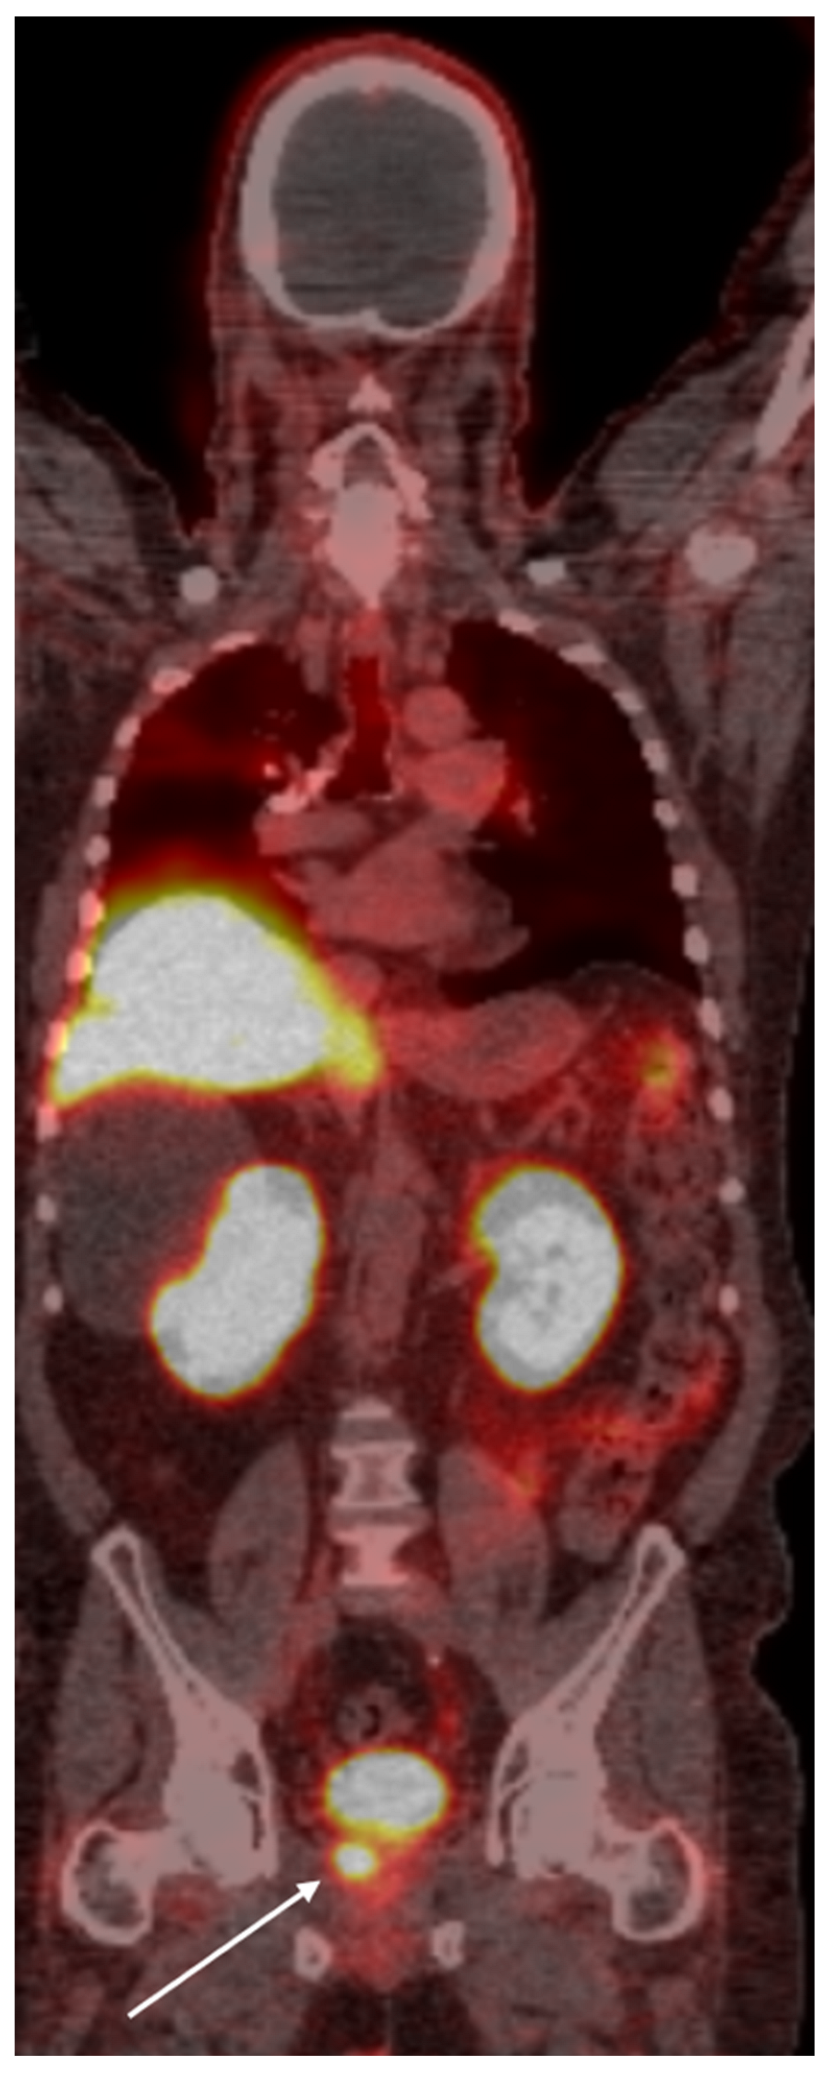

4. PSMA PET Imaging

- Adnan, A.; Basu, S. PSMA Receptor-Based PET-CT: The Basics and Current Status in Clinical and Research Applications. Diagnostics 2023, 13, 158. [Google Scholar] [CrossRef]

- Roberts, M.J.; Maurer, T.; Perera, M.; Eiber, M.; Hope, T.A.; Ost, P.; Siva, S.; Hofman, M.S.; Murphy, D.G.; Emmett, L.; et al. Using PSMA imaging for prognostication in localized and advanced prostate cancer. Nat. Rev. Urol. 2023, 20, 23–47. [Google Scholar] [CrossRef]

- Jochumsen, M.R.; Bouchelouche, K. PSMA PET/CT imaging in prostate cancer: Impact on clinical management and patient outcomes. Clin. Nucl. Med. 2024, 49, 1–10. [Google Scholar]

- Houshmand, S.; Salavati, A.; Solnes, L.B. Clinical applications of PSMA PET in prostate cancer management. PET Clin. 2023, 18, 1–18. [Google Scholar]

- Fendler, W.P.; Calais, J.; Eiber, M.; Flavell, R.R.; Rettig, M.B. PSMA PET for prostate cancer imaging: The current status and future directions. J. Nucl. Med. 2023, 64, 28–37. [Google Scholar]